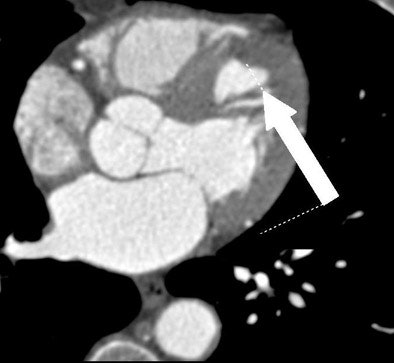

| All images were acquired in a 62-year-old man presenting to the hospital for evaluation of chest pain. Above, contrast-enhanced, retrospectively ECG-gated 64-slice-CT angiogram shows (arrow) hypoattenuation of the anteroseptal wall. All images courtesy of Dr. Christian Thilo. |